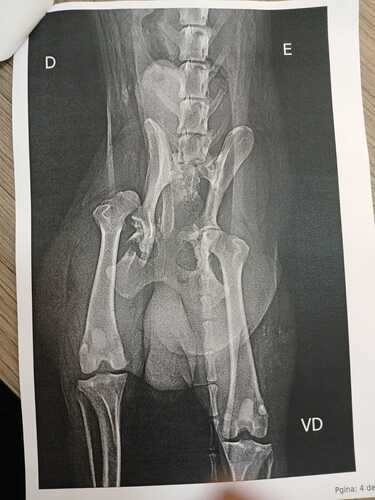

Oi, meu nome é Laura, abri esta Vakinha pois preciso arrecadar R$ 7.000,00, pois meu cachorro Hatchi, de oito anos, foi atropelado, atualmente o estado do Hatchi é cirúrgico, pois tiveram algumas fraturas, está utilizando sonda para urinar e estamos forçando ele agora com uso de laxante para poder defecar, está com muita dor e usando morfina via soro. Começou a se alimentar um pouco no domingo, 09/03 com frango desfiado.O Hatchi foi atropelado na sexta, dia 07/03, vimos nas câmeras que foi em questão de minuto, ele fugiu e o carro passou por cima dele, sem nenhum amparo. Internamos ele no mesmo dia, fizemos todos os exames necessários e vimos que ele fraturou o cóccix, pélvis, rabo e uma luxação no coxofemoral. Ontem, dia 10/03, trocamos ele de clínica, ele estava na Clínica Igara e agora foi para a Clínica Univet por questões financeiras, pois fizemos vários orçamentos da cirurgia. Os gastos e orçamentos estarão todos anexados aqui, e iremos ter o custo de remédios e de fisioterapia no pós operatório.Este ano já tivemos gastos com outra cachorra que adotamos da enchente, no qual também preciso operar um lipoma na barriga, temos o total de 6 cachorros adotados, e gostaríamos de pedir ajuda com o Hatchi.Qualquer ajuda é bem vinda!